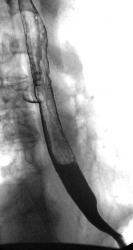

Пищевод.

дивертикулы пищевода

Изображение  Изображение